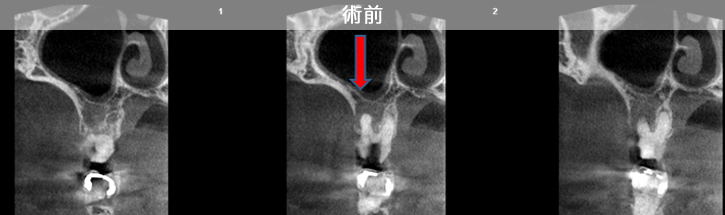

原因は赤の矢印が指す、根の周りの病巣でした。

治療後は青い矢印が指す場所には、黒い病巣が消失しています。

| 治療説明 | 自覚症状で歯が浮いた感じがしていました。上顎大臼歯・頬側根の根尖部にX線透過像の病巣があります。根充剤を除去・拡大清掃・根管充填を行いました。根尖から根充剤がはみ出ていますが、根尖部のX線透過像は見られなくなりました。そこ後、自覚症状もなくなりました。 |

|---|---|

| 治療期間 | 6〜24ヶ月 |

| 治療費用 | 150,000〜300,000円 |

| 治療に伴うリスク | 根管内からの治療で根尖病巣が治らない場合は、外科的に根尖病巣を除去する必要があります。 再根管治療を繰り返す場合、歯根の厚みが薄くなり、歯根破折のリスクが高まります。 |